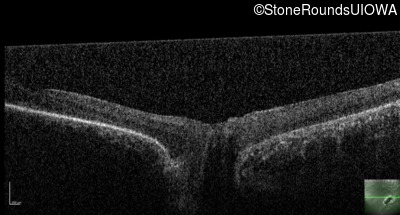

Optical Coherence Tomography - Right - Light Perception

Exemplar